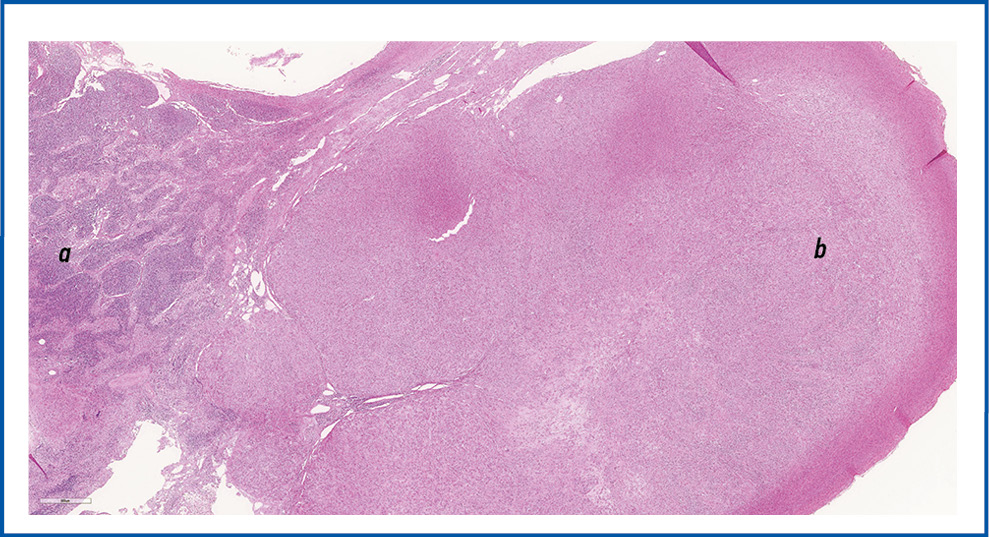

При патологоанатомическом исследовании макропрепарата: матка представлена многоузловым конгломератом общим размером 30×28×20 см, при разрезе матки выявлялось множество плотных узловых образований желтовато-серого цвета, волокнистого вида, размером от 0,5 до 2 см. Образование располагалось преимущественно по передней стенке ТМ с прорастанием всех слоев. В яичниках и тубоовариальных связках слева и справа определялись множественные опухолевые узлы (ОУ) аналогичного строения ОУ в матке, размерами от 1 до 13 см. В тазовых ЛУ справа и слева обнаружены аналогичные плотные узлы от 0,5 до 1 см в диаметре. Образование мягких тканей левого бедра представлено ОУ аналогичного строения размером 3×2,5×1,5 см. При микроскопическом исследовании все образования представлены доброкачественной опухолевой тканью в виде переплетающихся гладкомышечных волокон с низкой митотической активностью опухолевых клеток (ОК) без полиморфизма, очагов некроза и кровоизлияний (рис. 8). Морфологическая картина соответствовала ЛММ, мягких тканей левого бедра, тазовых ЛУ (рис. 9), обоих яичников и тубоовариальных связок ТМ.

Рис. 9. Метастаз ЛМ в парааортальный ЛУ: a – остаточная ткань ЛУ; b – метастатическая ткань ЛМ. Окраска гематоксилин-эозином, ×100.

Fig. 9. Metastasis of LM to the para-aortic lymph node: a – residual tissue of the lymph node; b – metastatic tissue of LM. Hematoxylin and eosin staining, ×100.